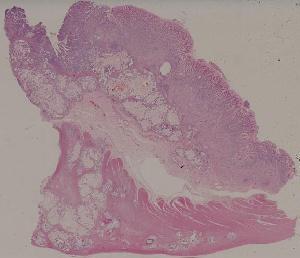

66.活动性结节性肝硬化